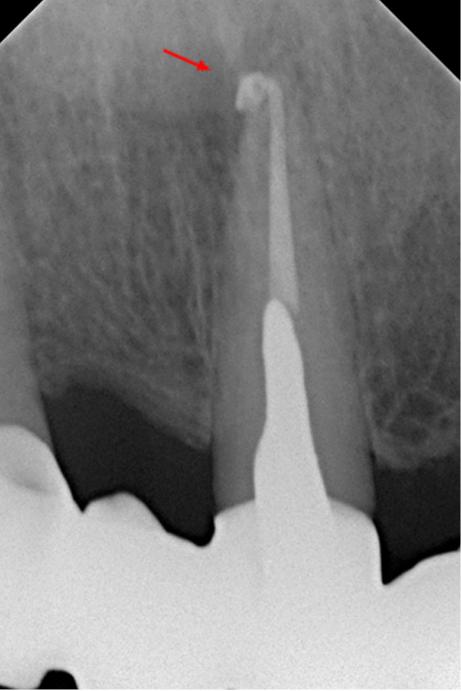

На контрольном снимке через 12 месяцев после лечения отмечается репарация тканей в области верхушки 21 зуба (снимок 4). Жалобы отсутствуют.